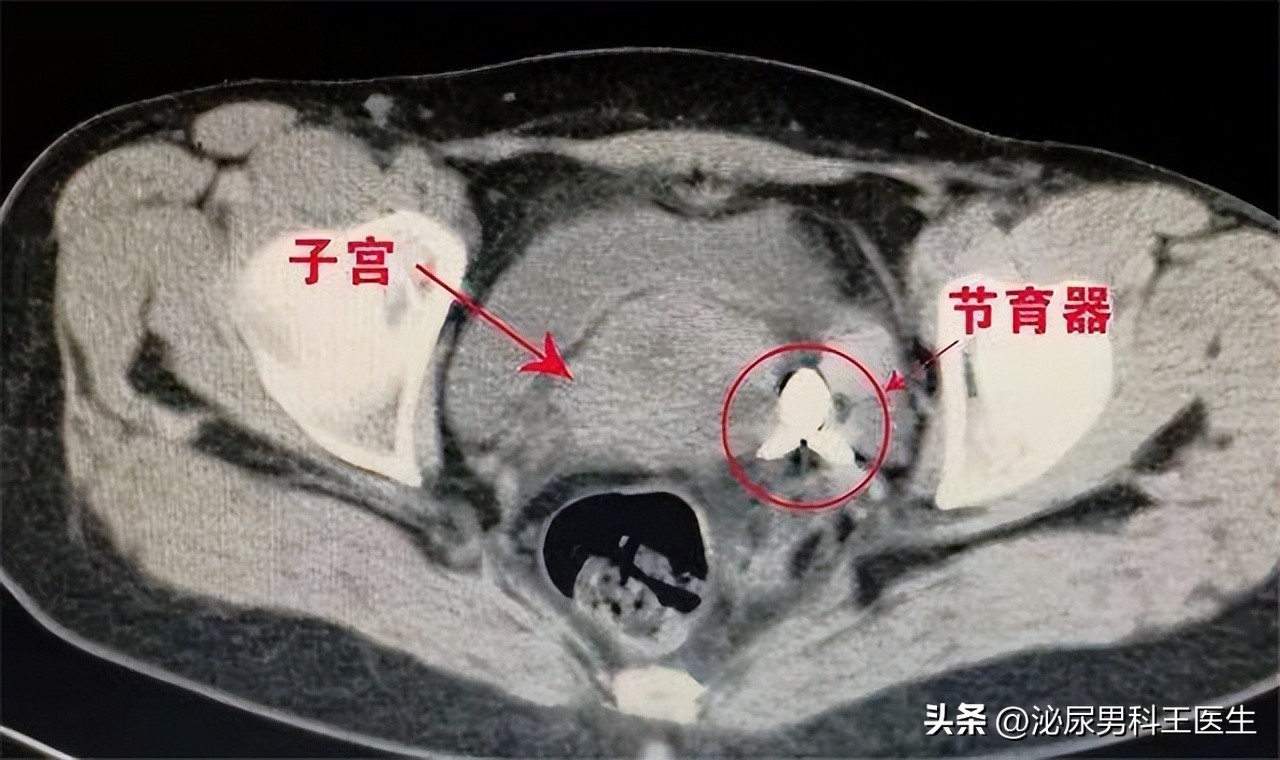

通过腹部影像检查发现李女士子宫内的节育环嵌顿至子宫基底,而且在周围形成大量脓性物质, 询问李女士节育环使用年限是否到期,放置节育环后有无复查, 通过林女士的回答得知节育环已到期,而且李女士并没有复查过,最终确诊为是由节育环嵌顿导致的子宫腔内感染。

女性随着年龄增长,子宫肌层会发生变化,肌层会出现衰退的现象,子宫腔会不断缩小,导致节育环长到子宫肌层内。节育环一般放置在子宫腔内,宫腔成倒三角形,上宽下窄,上部两端连接输卵管,放置节育环后会影响输卵管运输卵子,起到避孕的效果,也有部分节育环放置在阴道后穹窿部位,这个部位放置过深也会损伤子宫肌层。

超年限使用节育环可能会发生子宫嵌顿,节育环破坏子宫肌层后还可能损伤子宫外的脏器, 发生嵌顿后节育环的位置已经偏离子宫腔内中心,机体在活动时会加重节育环偏离,节育环穿破子宫后会造成子宫穿孔,随后可能破坏与子宫相连的脏器,例如盆腔,膀胱等脏器, 因此避免超年限使用节育环。